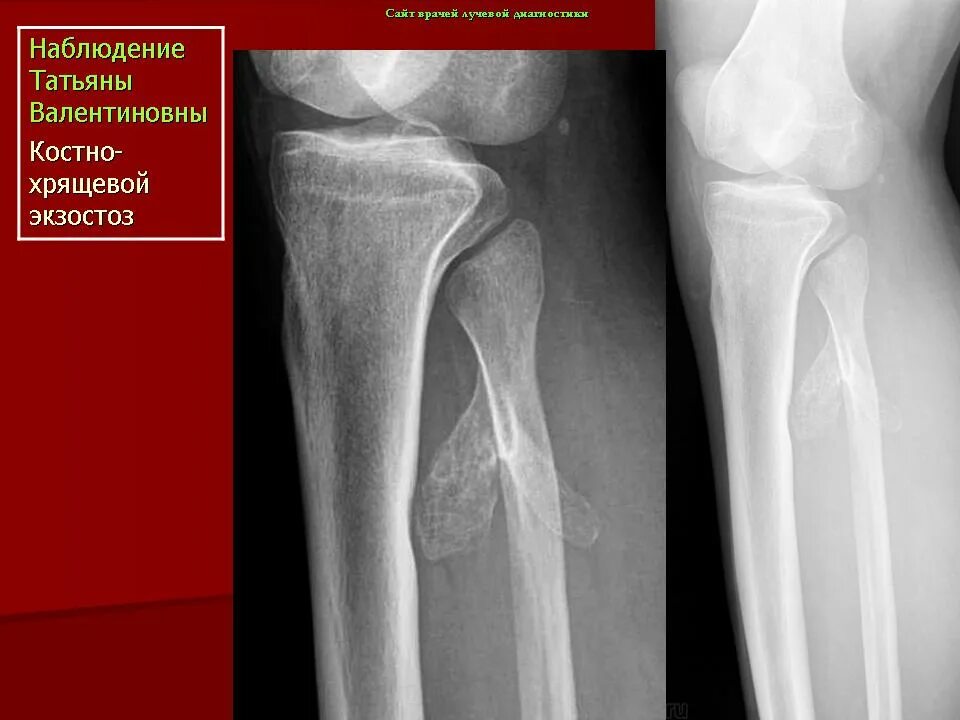

Экзостоз мкб 10